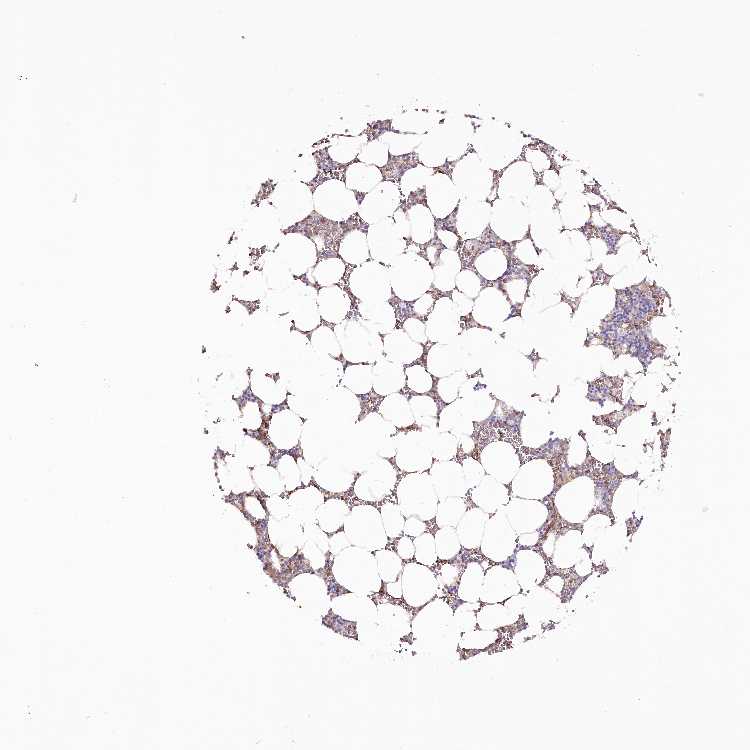

BONE MARROW - Antibody stainingi

Antibody staining in the annotated cell types in the current human tissue is reported as not detected, low, medium, or high, based on conventional immunohistochemistry profiling in selected tissues. This score is based on the combination of the staining intensity and fraction of stained cells. Each image is clickable and will lead to virtual microscopy that enables deeper exploration of all samples and also displays staining intensity scores, fraction scores and subcellular localization as well as patient and tissue information for each sample.

Antibody HPA030665Antibody HPA068563Antibody CAB037231

Hematopoietic cells Not detectedNot detectedNot detected